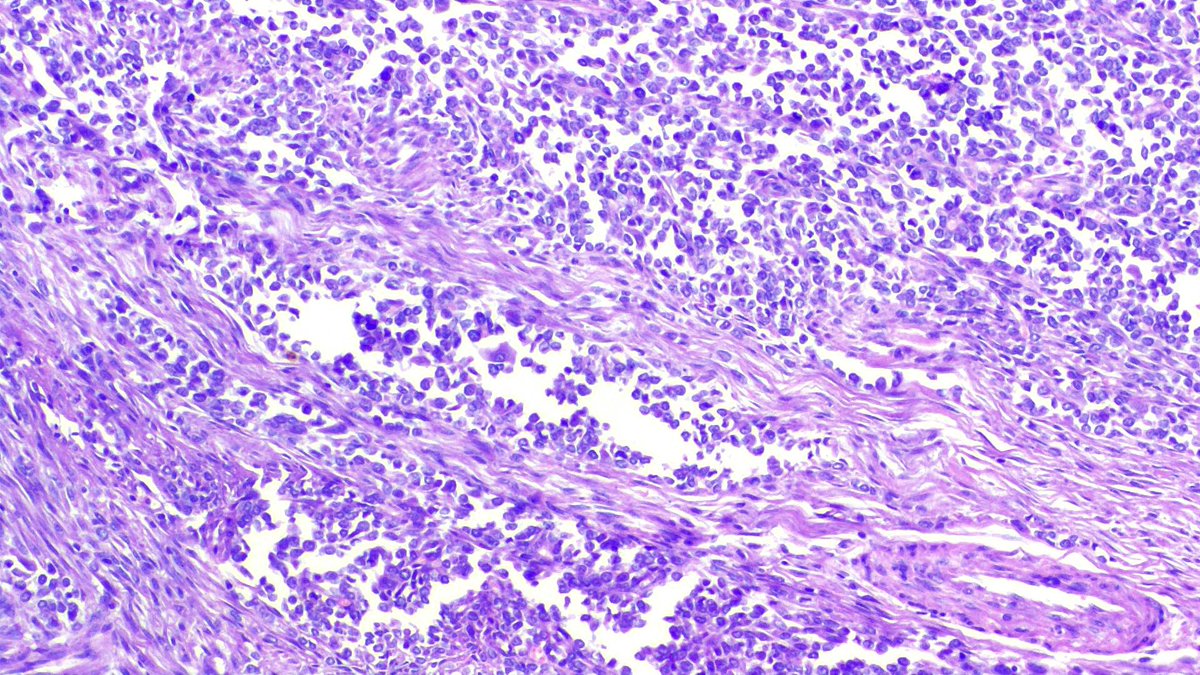

A finding in a D&C specimen from a missed abortion. X4 and X10 Diagnosis? #Pathology #Pathresidents #Path2Path #Pathmatch25 #Pathmatch26 #OBGYNPath

leon_metlay's tweet image. A finding in a D&C specimen from a missed abortion.

X4 and X10

Diagnosis?